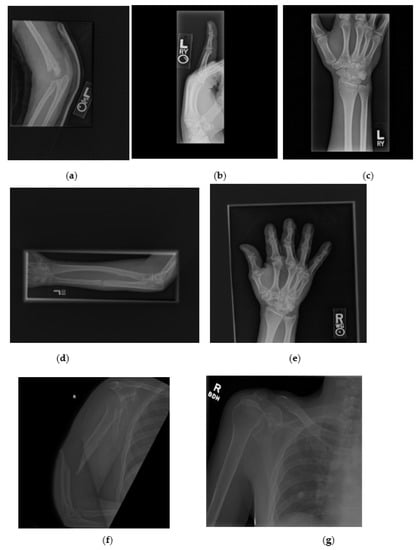

The dataset used in this paper is the publicly available MURA dataset introduced by Rajpurkar et al. [12]. MURA includes seven different musculoskeletal categories, namely wrist, hand, elbow, shoulder, forearm, finger, and humerus. The dataset contains 40,005 images split into 92% for training and 8% for testing. The original size of the images is not constant and ranges from 512 × 512 pixels to 97 × 512 pixels. The file extension of the images is .png. In Figure 3, a sample of each fracture type is shown.

Figure 3.

Samples of each fracture type from MURA dataset: (a) Fractured elbow. (b) Fractured finger. (c) Fractured wrist. (d) Fractured forearm. (e) Fractured hand. (f) Fractured humerus. (g) Fractured shoulder.